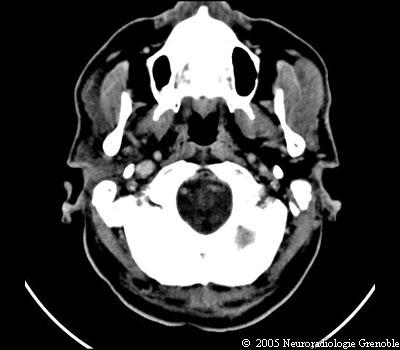

Radioanatomie TDM de l'encéphale

TDM cérébrale sans injection